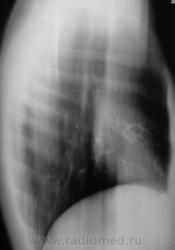

Первое исследование.